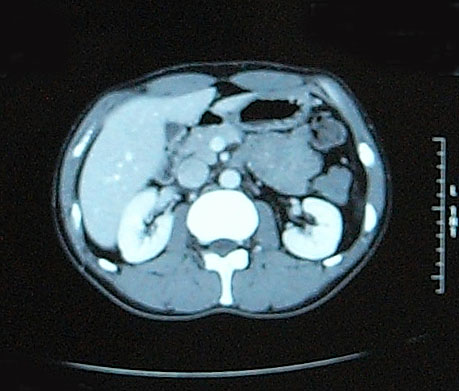

問題なし 【腫瘍マーカー】 HCGβ:<0.1 問題なし 【中性脂肪】 219→137 基準内(38-193)に入った 今回、検査画像をデータでもらってきた。 後腹膜の転移した箇所の前後4枚を2003年から2010年まで並べてみた。 http://gomatsushita.gozaru.jp/ct/album/index.html 2006/7/18の画像を見ると腫瘍がハッキリ見える。 BEP2クール後の9/27の画像では明らかに縮小もしくは消滅。

今回からCTの造影剤はありませんでした。

勘違いしてた・・・ なので単純CT。 横になって撮るだけなので非常に楽ですね。その分撮影される画像も解像度が低くなりますが・・・ しかし、思えば2005年末頃の単純CTからリンパ転移が疑われ始め、その次からはずっと造影剤を使用したCTだったわけだ。 2008年末の今、やっとそこへ戻ってきたという感じがした。 検査後の帰り、病院の最寄り駅のパン屋で朝食。 改札横に店があるのでガラス越しに行き交う多くの人を眺めながら思う。 2006年の入院中、ヨメも色々思いながらここを通ったんだろう、と。 何ヶ月も。 暑い日も雨の日も。 ただただ「感謝」あるのみです。 本日の検査結果は12/8。